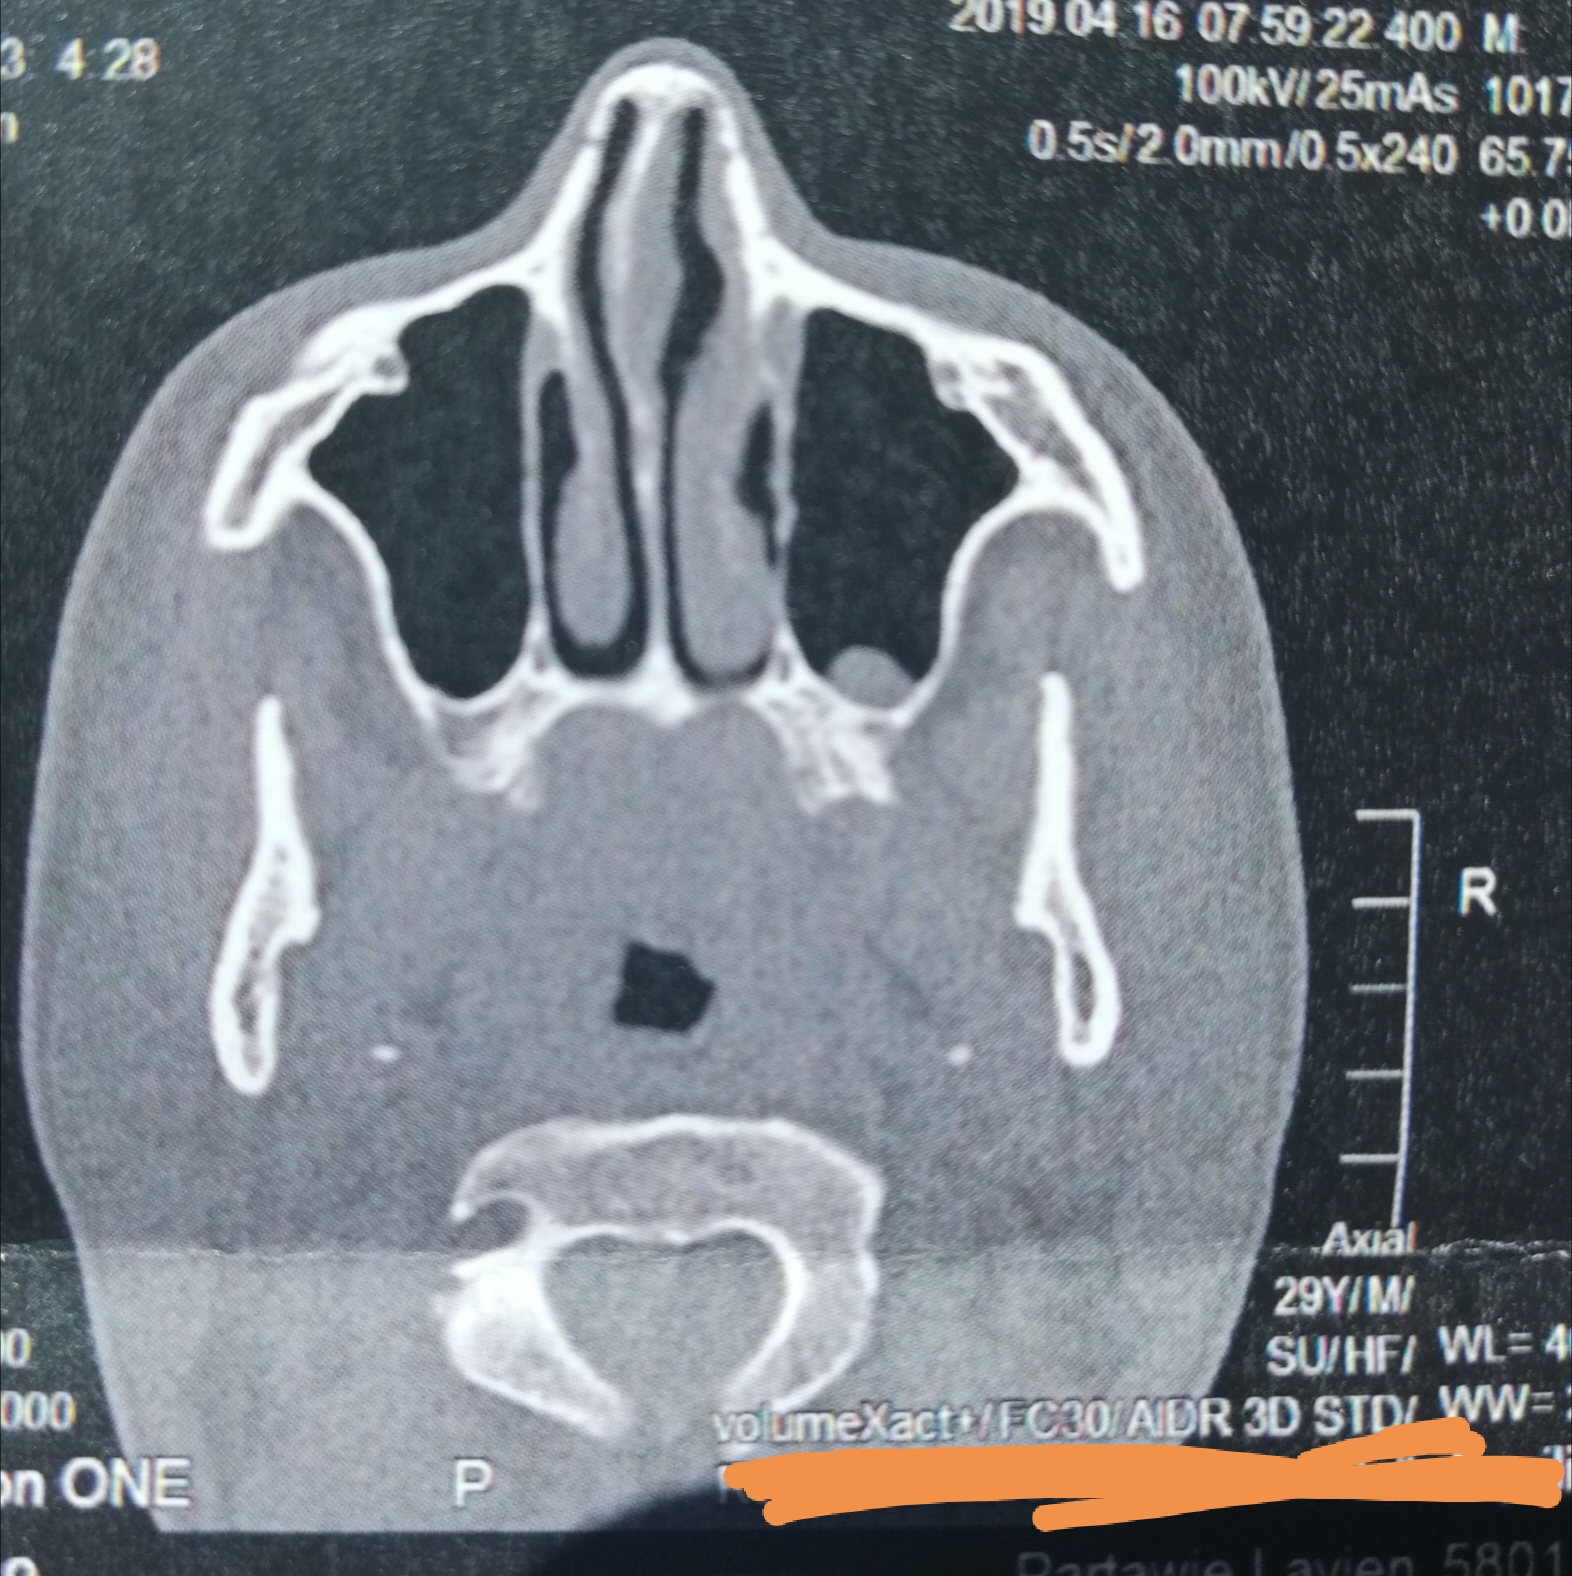

CT der Nasennebenhöhlen /Nase, alles ok? (kernspintomographie)

Source: www.gesundheitsfrage.net